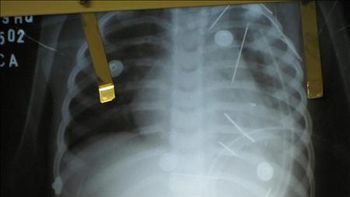

Un niño catamarqueño pasó casi un mes con un alfiler de gancho incrustado en su garganta porque los distintos médicos que lo atendieron en la localidad catamarqueña de Rincón no lo habían detectado, tras lo cual fue operado con éxito en Córdoba.

Eugenia Porta, la madre del niño que tiene diez meses, lamentó las demoras en localizar el problema al señalar que "si le hubieran hecho la primera vez una radiografía, le hubieran detectado lo que tenía".

El bebe fue operado en los últimos días en una clínica de Córdoba donde le extrajeron el objeto metálico.

Así, la familia viajó de urgencia a la ciudad de Catamarca y en una clínica le colocaron una sonda con cámara que localizó el objeto metálico, tras lo cual fue derivado y operado en Córdoba.